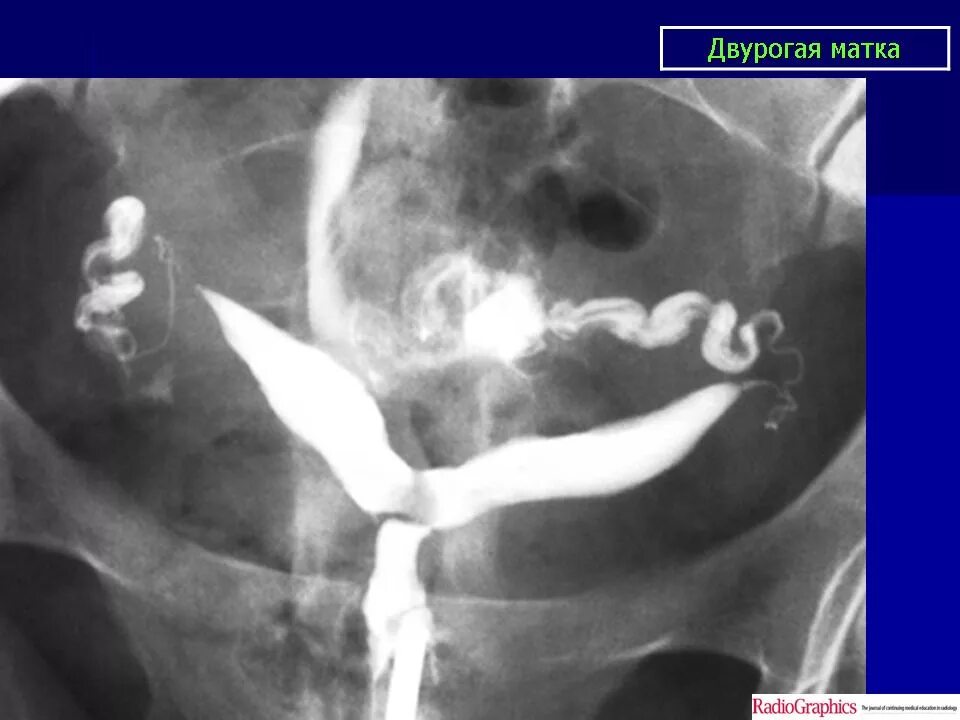

Аномалия полов орган